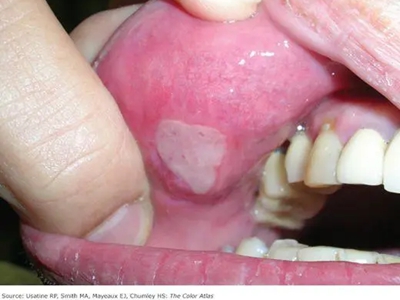

梅毒黏膜斑是二期梅毒最常见的口腔损害。可发生在口腔黏膜的任何部位,以唇黏膜最多见,其次为软腭、舌背、舌底等部位。损害呈灰白色、光亮而微隆的斑块,圆形或椭圆形,直径约1cm,边界清楚。易发生糜烂或浅表溃疡,表面覆盖灰白色假膜,周围有红晕。黏膜斑常为多个,内含有大量梅毒螺旋体。